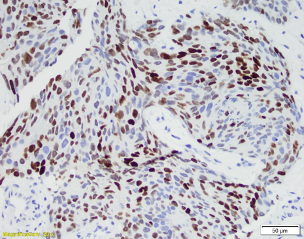

Patient is a 60-year-old male with a “bladder tumor.” Multiple nodules were present in the lung, liver and pelvic lymph nodes. A CT guided biopsy was performed, targeting the hepatic nodules. P40, synaptophysin and chromogranin are negative. MSI studies show loss of MLH1 and PMS2, with retained MSH2 and MSH6.

Picture1 WIN 20201023 14 55 38 ProWIN 20201023 14 56 49 Pro 2020-10-26T17:46:01Z

The patient has metastatic prostate cancer. Immunohistochemical stains are supportive for this diagnosis. NXK3 .1 is helpful in distinguishing poorly differentiated prostatic carcinoma from urothelial. NKX3.1 is a more sensitive and specific than PSAP. Aberrant staining of GATA 3 can be seen in subset set of prostatic carcinomas.  This potential pitfall that may be avoided with more specific and sensitive markers for prostate cancer. MSI loss may be seen in patients with prostatic cancer, however currently there is no increased risk in patients with a family history of prostatic cancer.